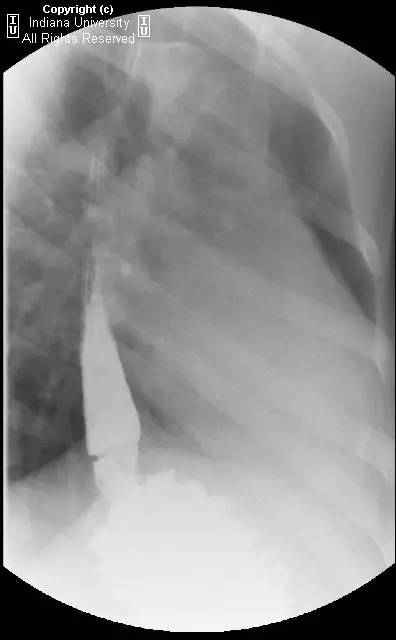

【影像学表现】可见小滑动性食管裂孔疝,食管远端胃食管连接处上方亦见一小的边界清晰的环形充盈缺损,钡剂通过顺利,但直径13mm不透射线的药片吞水后仍在充盈缺损上方崁顿,数分钟后进入胃。

【诊断】Schatzki环(舍茨基环)并滑动性食管裂孔疝

Schatzki ring andsliding hiatal hernia.